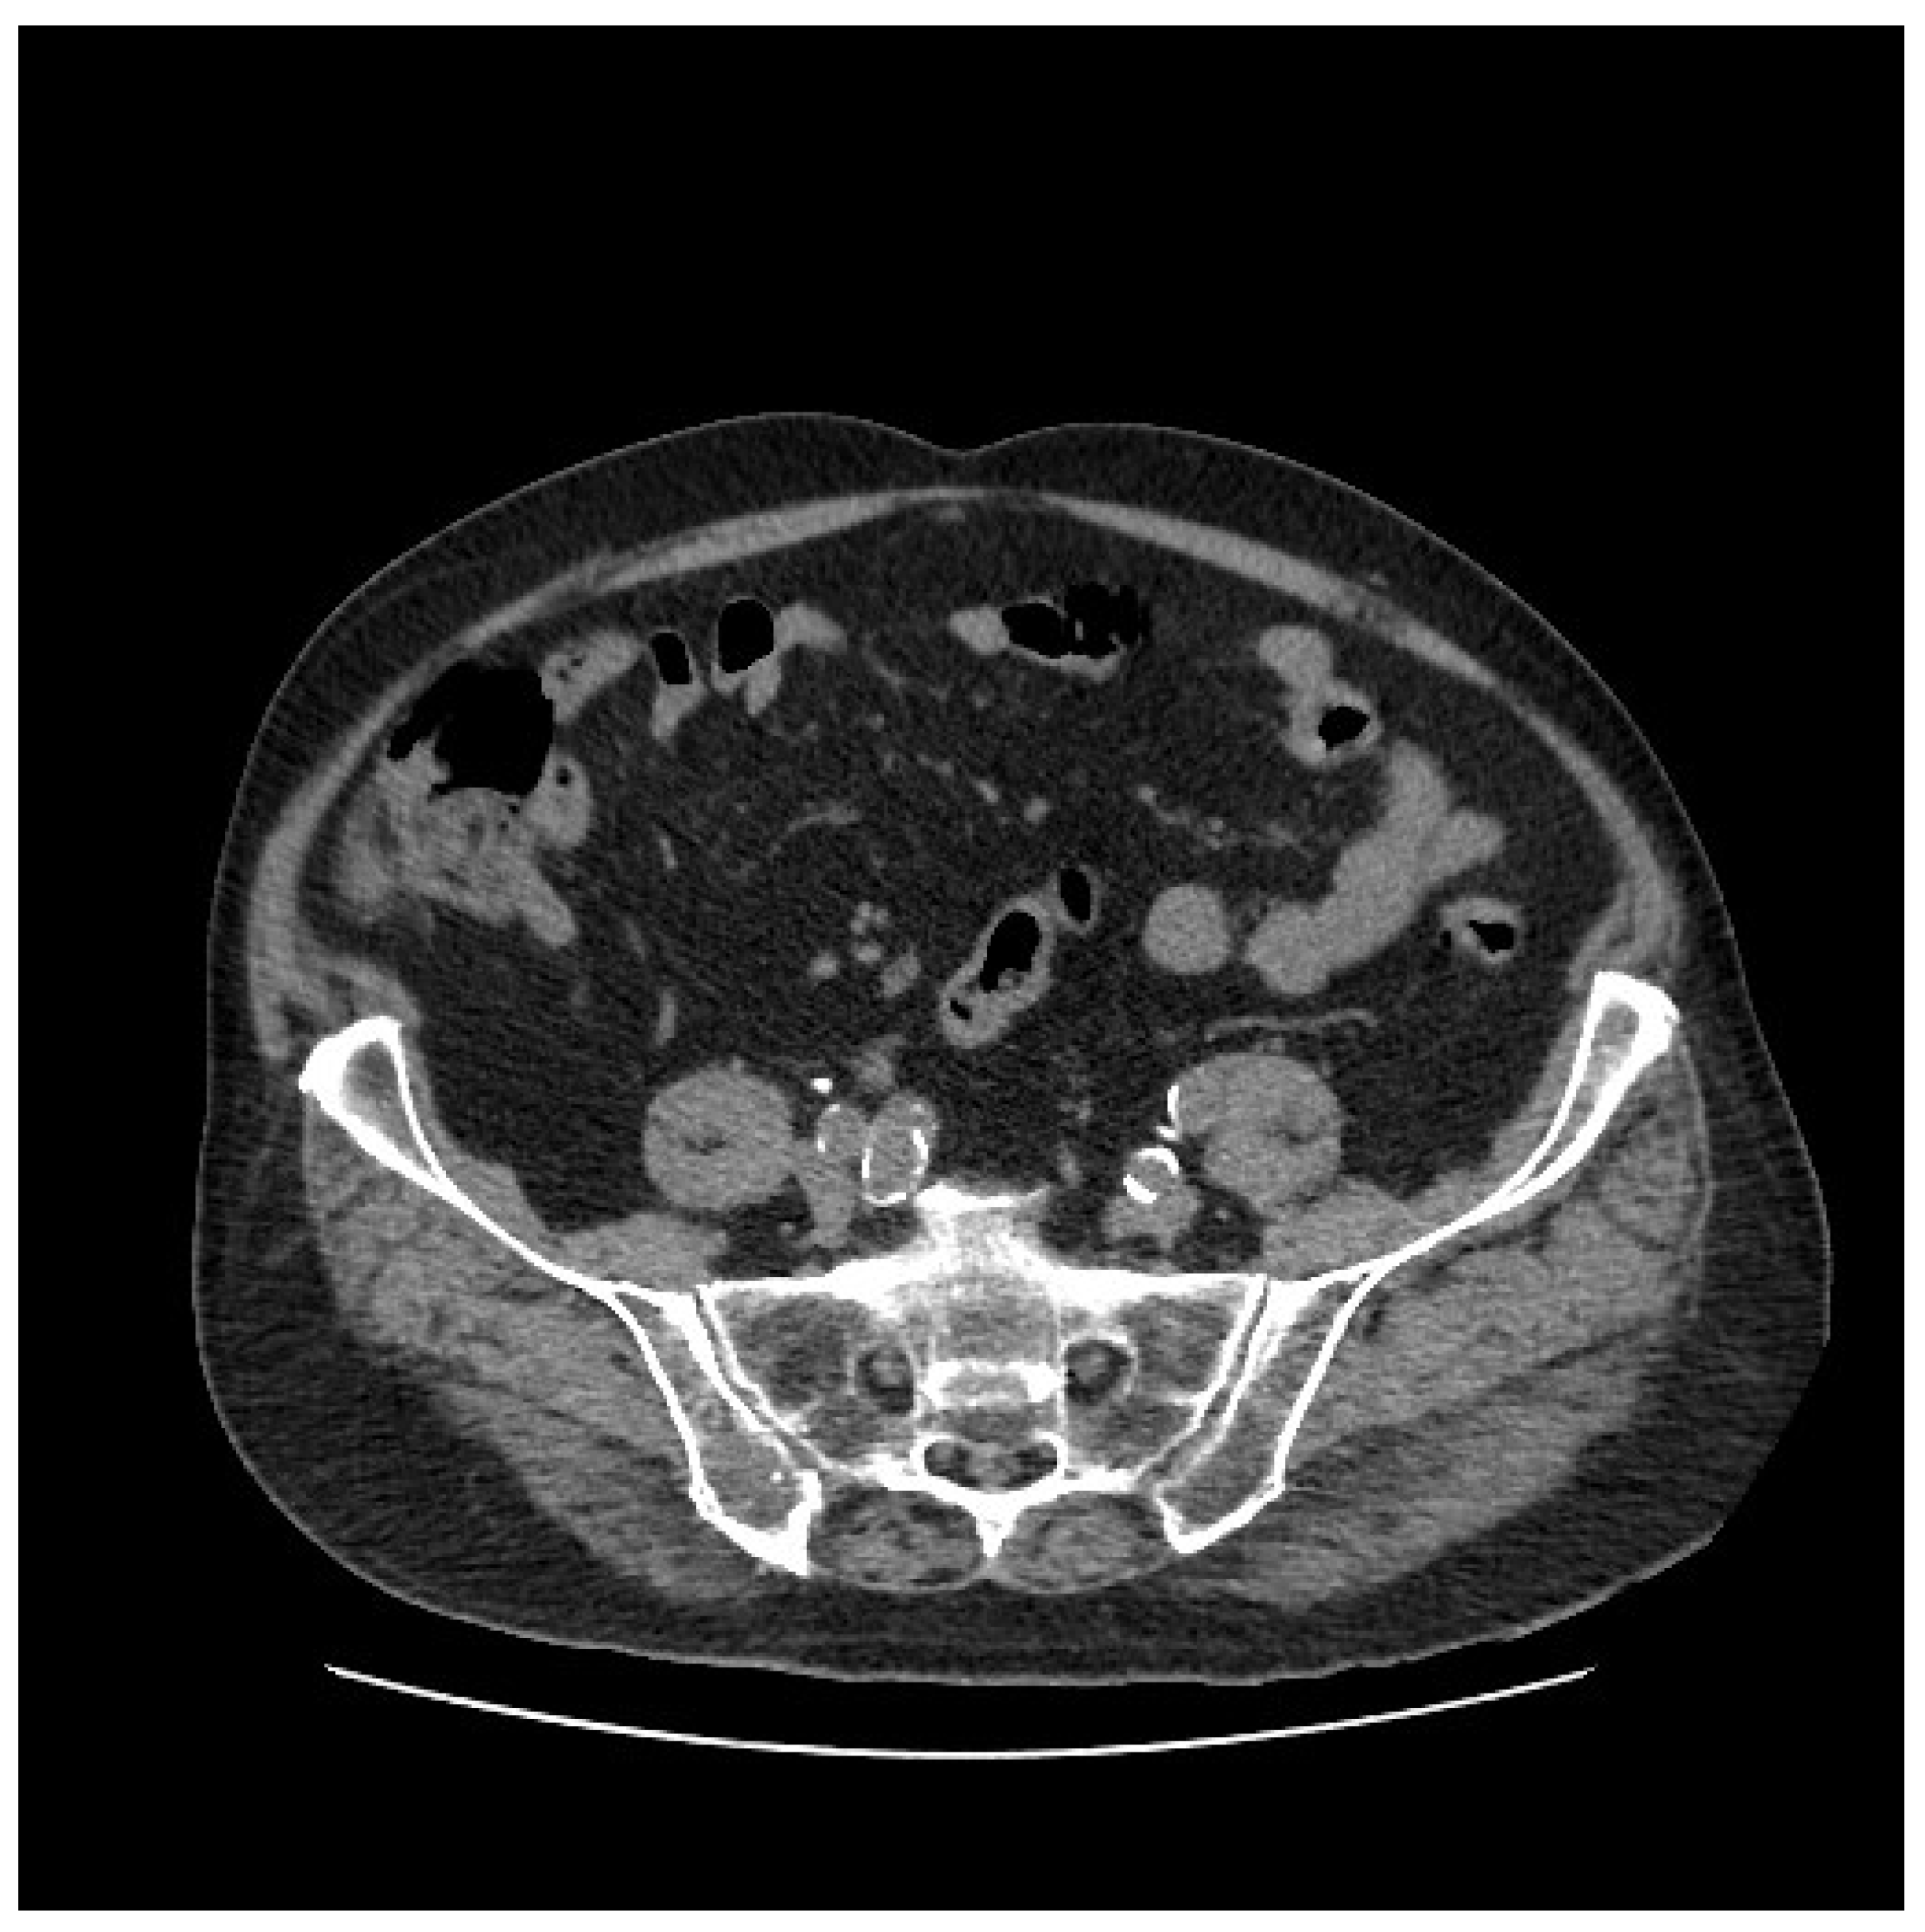

An intravenous contrast-enhanced abdominal CT scan demonstrated an “aneurysmatic dilatation of the right iliac bifurcation”, predominantly affecting the IIA, with a diameter of 4 cm and evidence of extraluminal extravasation of the contrast media, indicative of a rupture. Additionally, blood effusion was noted in the perianeurysmal space, perihepatic area, right paracolic gutter, and pelvic cavity. The patient was promptly taken to the operating theatre, where permissive hypotension and hypovolemia were employed. See Figure 1.

Figure 1. Multiplanar reformation (MPR view in axial (A), coronal (B), sagittal (C)) and 3D reconstruction (D) of preoperative CT angiography, showing right internal iliac artery rupture (highlighted with arrows).